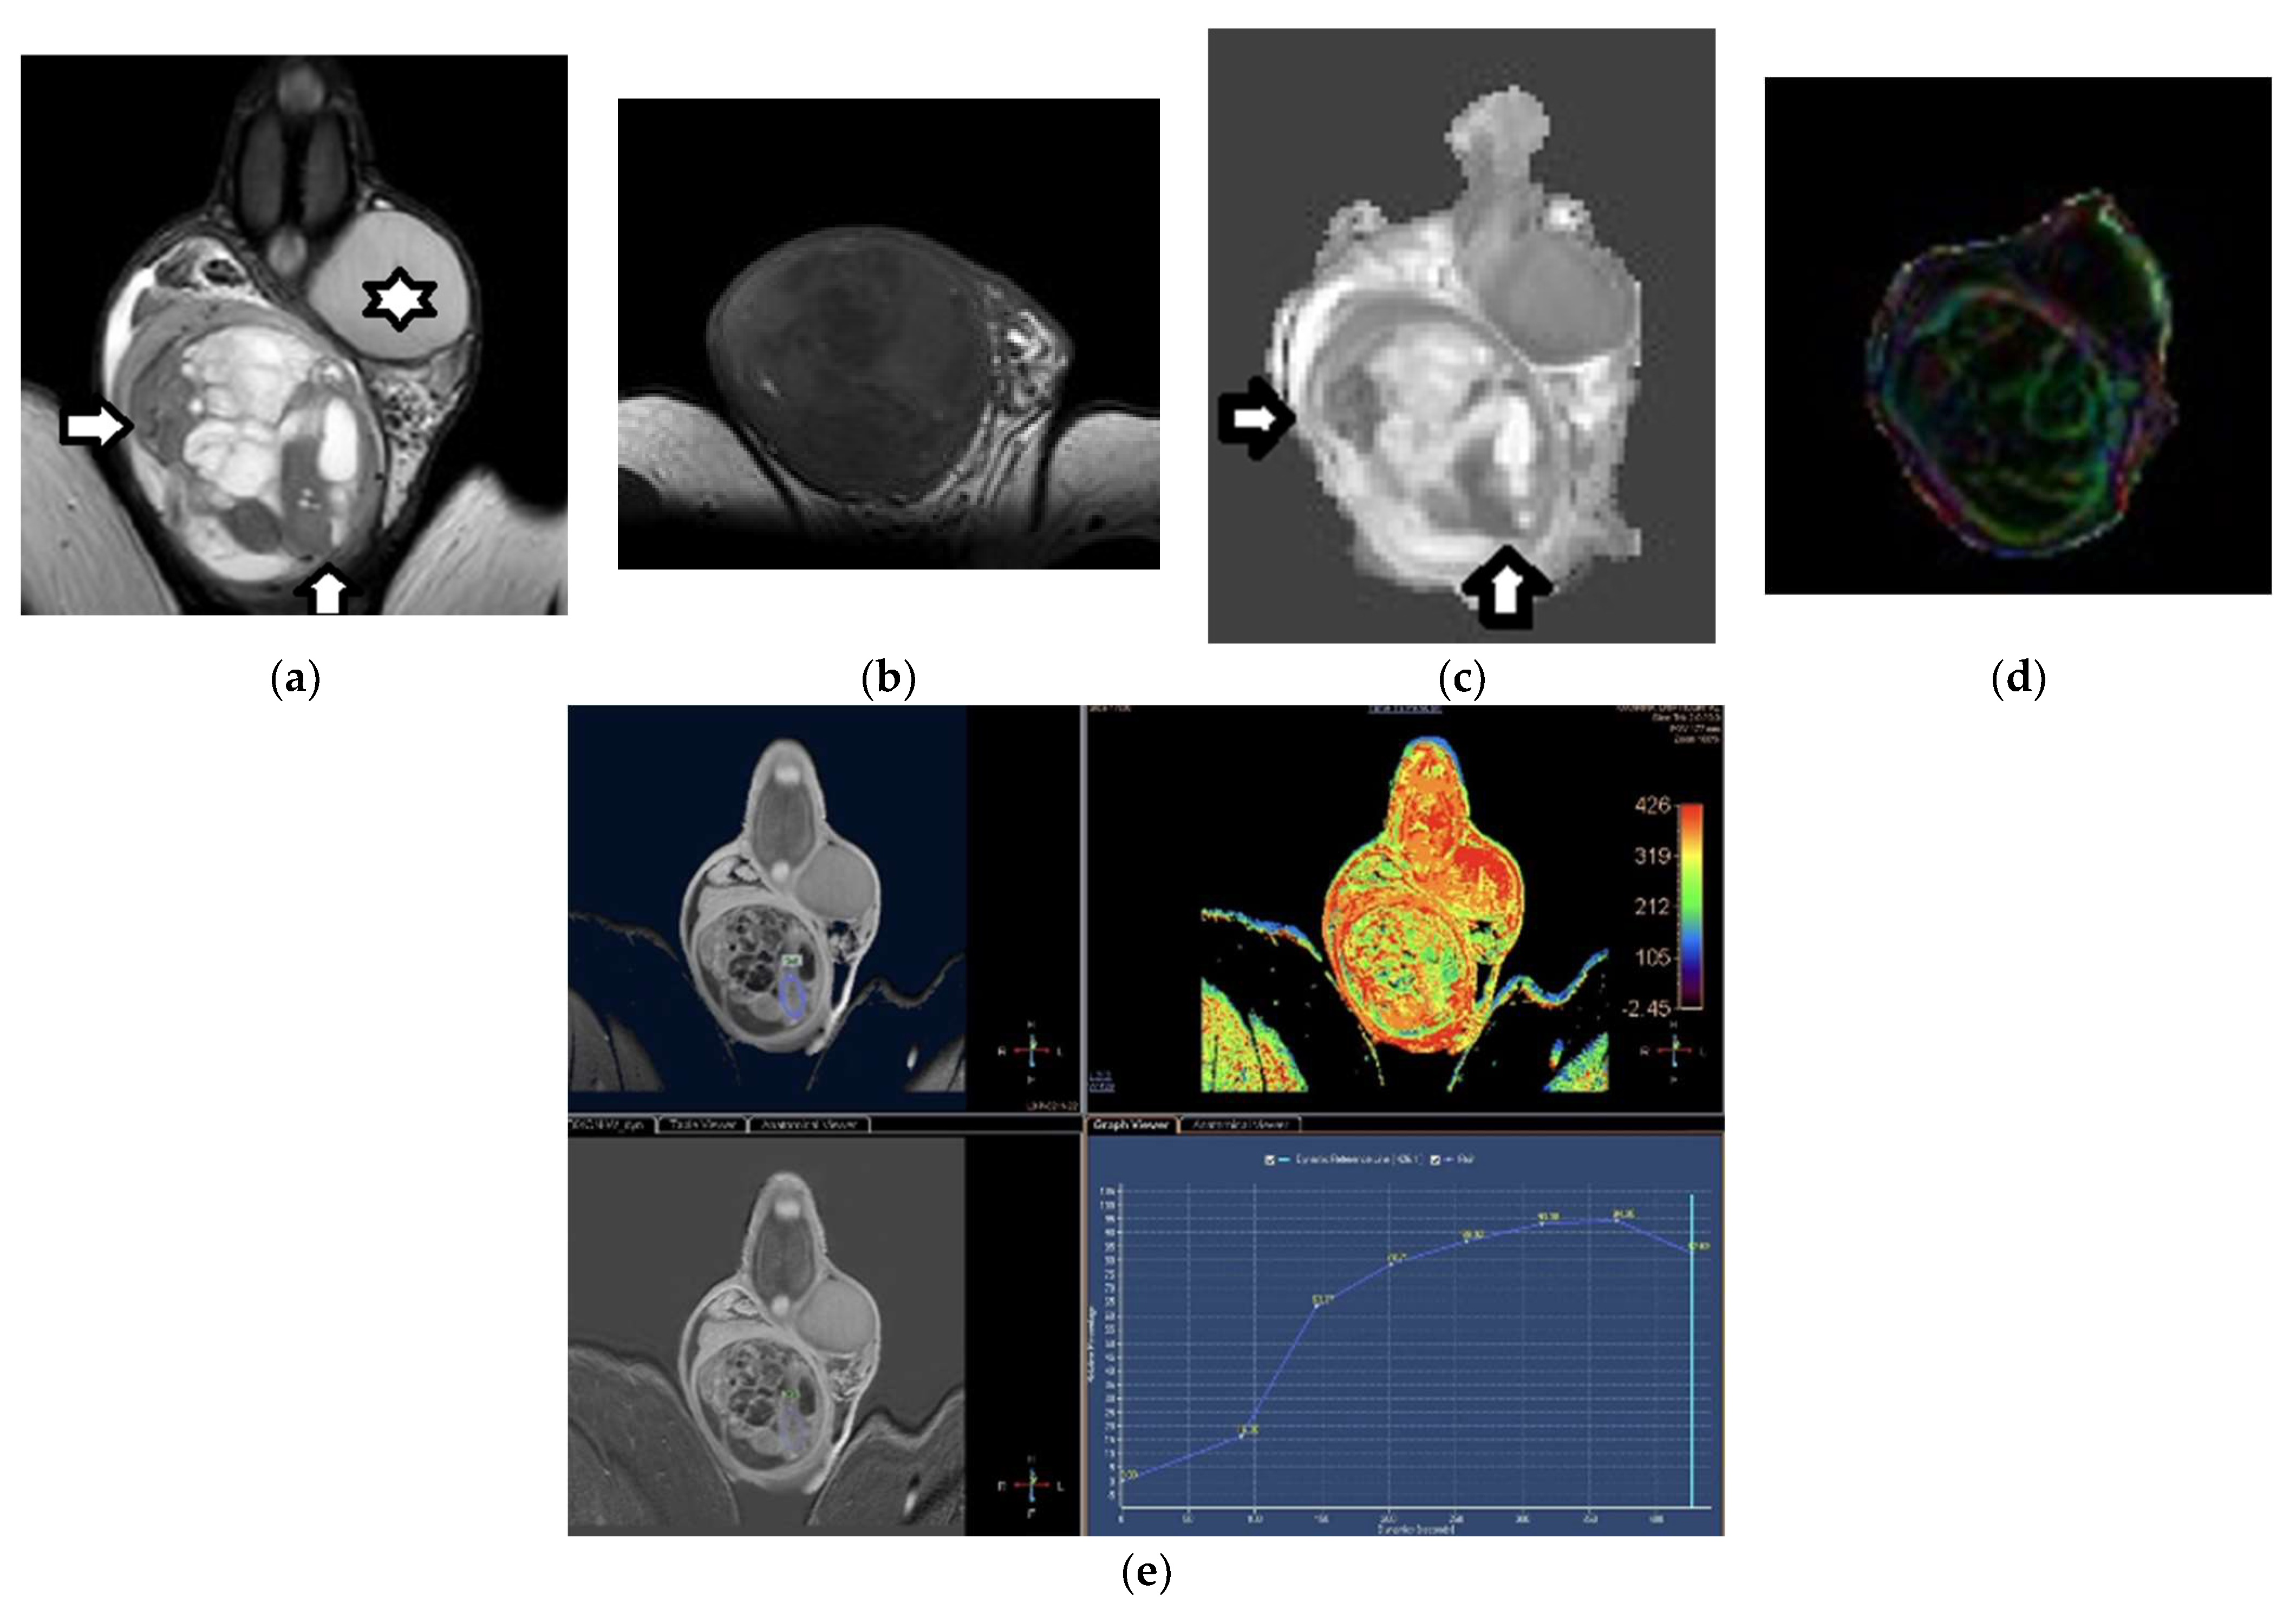

3.1. MRI Findings of TGCTs

3.2. Epidermoid Cysts

3.3. Testicular Lymphoma

4. Characterization of Testicular Tumors: Germ-Cell versus Sex-Cord Stromal Testicular Tumors

Sertoli-Cell Tumors

5. Histological Characterization of TGCTs

6. Local Staging of TGCTs